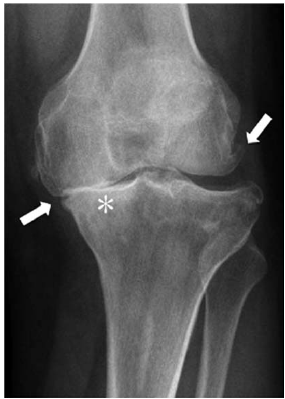

Uma paciente de 63 anos de idade compareceu ao consultório queixando-se de dor nos joelhos há cerca de cinco anos. Nega trauma. Refere que a dor começou a piorar nos últimos três meses. Relata ainda diabetes mellitus, e que seu joelho começou a entortar (sic) e que, quando acorda, o seu joelho frequentemente está rígido.

Outra classificação muito difundida dessa doença é a descrita por Ahlbäck. Segundo esse autor, classifica-se a radiografia representada na figura da questão 25 como grau:

Considere que a paciente do caso clínico relatado realizou o exame representado na figura. De acordo com a classificação de Kellgren e Lawrence, trata-se do grau

A classificação radiográfica Kellgren e Lawrence se baseia em três parâmetros que são